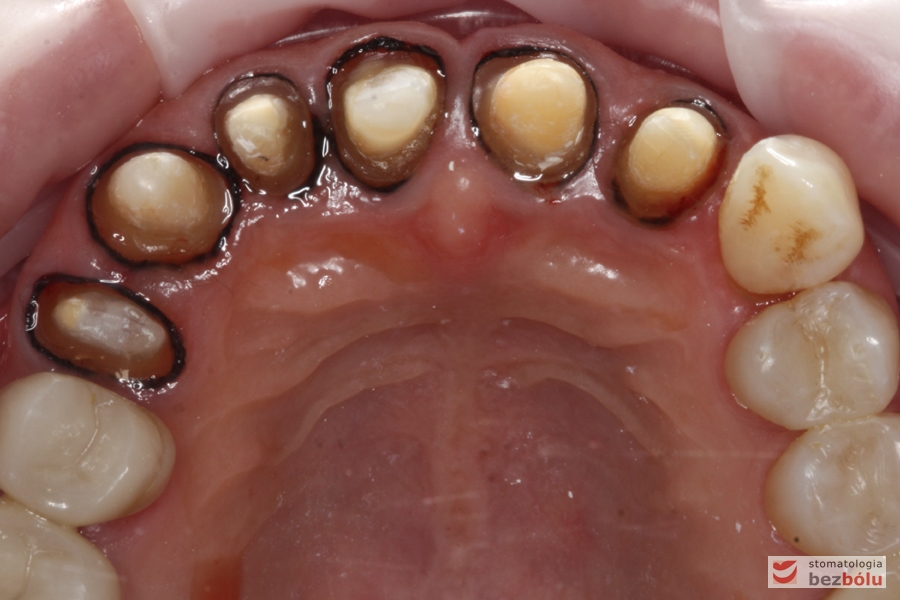

Powierzchnia okluzyjna łuku górnego - sześć filarów protetycznych tuż przed zacementowaniem koron

Powierzchnia okluzyjna łuku górnego – sześć filarów protetycznych tuż przed zacementowaniem koron